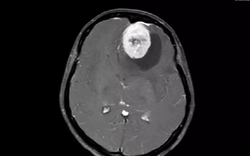

• Nam sinh trung học sốt 5 ngày rồi tử vong, bác sĩ cảnh báo: Bệnh phổ biến nhưng không thể xem nhẹ

Nam sinh trung học sốt 5 ngày rồi tử vong, bác sĩ cảnh báo: Bệnh phổ biến nhưng không thể xem nhẹ

Nam sinh xuất hiện sốt và nhiều biểu hiện khó chịu nhưng trì hoãn điều trị suốt 5 ngày. Khi được gia đình đưa vào khoa cấp cứu, em đã trong tình trạng kiệt sức toàn thân. Kết quả kiểm tra khiến bác sĩ không khỏi bàng hoàng.